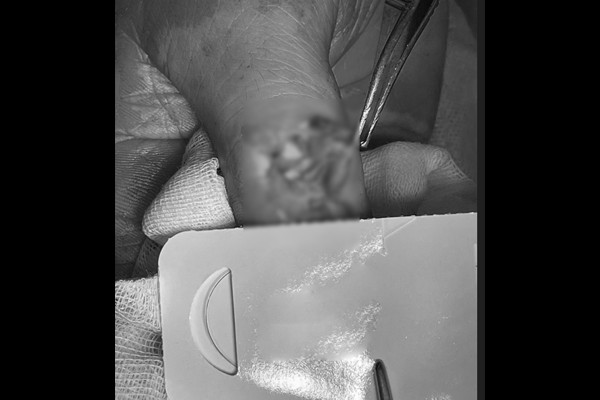

수술실 사진을 보시면 골절로 인해 피부가 터져있는 것이 확인됩니다.

골절된 뼈를 맞추고 뼛조각을 원래 위치로 돌린 후 떨어져나간 힘줄(장무지신전건)을 원래 위치에 잘 부착해줍니다.